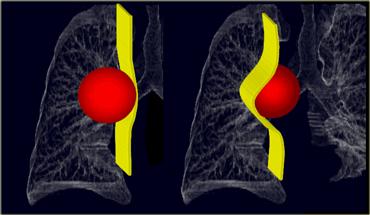

TRÁI: Một khối u phổi tiếp giáp bề mặt trung thất và tạo góc nhọn với phổi. PHẢI: Một khối u trung thất sẽ nằm bên dưới bề mặt trung thất, tạo góc tù với phổi.

Các đặc điểm sau đây cho thấy tổn thương có nguồn gốc từ trung thất:

- Khác với các tổn thương phổi, khối u trung thất sẽ không chứa dấu hiệu phế quản hơi.

- Bờ tiếp giáp với phổi sẽ tạo góc tù.

- Các đường trung thất (ngách azygô-thực quản, đường nối trước và sau) sẽ bị gián đoạn.

- Có thể kèm theo các bất thường ở cột sống, xương sườn hoặc xương ức.

Một khối u phổi tiếp giáp bề mặt trung thất sẽ tạo góc nhọn với phổi, trong khi một khối u trung thất sẽ nằm bên dưới bề mặt và tạo góc tù với phổi (Hình minh họa).